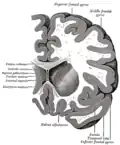

Structure

Along with the putamen, the caudate forms the dorsal striatum, which is considered a single functional structure; anatomically, it is separated by a large white-matter tract, the internal capsule, so it is sometimes also described as two structures—the medial dorsal striatum (the caudate) and the lateral dorsal striatum (the putamen). In this vein, the two are functionally distinct not because of structural differences, but merely because of the topographical distribution of function.

The caudate nuclei are near the center of the brain, sitting astride the thalamus. There is a caudate nucleus in each hemisphere of the brain. Each nucleus is C-shaped, with a wider "head" (caput in Latin) at the front, tapering to a "body" (corpus) and a "tail" (cauda). Sometimes a part of the caudate nucleus is called the "knee" (genu).[6] The caudate head receives its blood supply from the lenticulostriate artery; the tail of the caudate receives its blood supply from the anterior choroidal artery.[7]

The head and body of the caudate nucleus form part of the floor of the anterior horn of the lateral ventricle. The body travels briefly towards the back of the head; the tail then curves back toward the anterior, forming the roof of the inferior horn of the lateral ventricle. This means that a coronal section (on a plane parallel to the face) that cuts through the tail will also cross the body and head of the caudate nucleus.